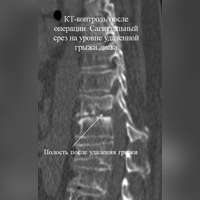

24 апреля 2018 года комбинированной бригадой хирургов (торакальных и нейрохирургов) выполнена операция по удалению оссифицированной грыжи межпозвонкового диска с компрессией спинного мозга на грудном уровне позвоночника.

Первым этапом через плевральную полость выполнили робот-ассистированный доступ к передним отделам позвоночника, с прецизионным выделением головки ребра, тела позвонка и межпозвонкового диска, резекцией головки ребра. Вторым этапом торакоскопически с использованием ультразвукового ножа удалили оссифицированную грыжу диска. Послеоперационный период гладкий, пациент выписан через 5 дней для продолжения лечения у невролога по месту жительства.